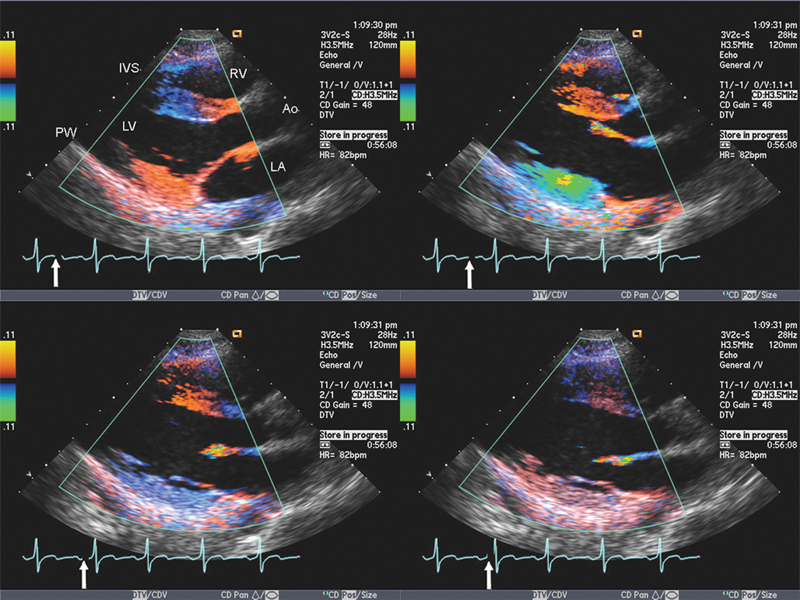

فحوصات تشخيصية لبعض امراض القلب والشرايين التاجية